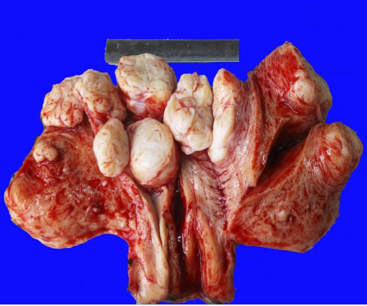

1. 畸胎瘤(teratoma)

畸胎瘤是来源于性腺或胚胎剩件中的全能细胞,多含有两个以上胚层的多种多样组织成分,排列结构错乱。

根据外观又可分为囊性和实性两种;根据其组织分化成熟程度不同,又分为皮样囊肿(dermoid cyst)、(也称成熟畸胎瘤或良性畸胎瘤)和不成熟畸胎瘤(恶性畸胎瘤)。畸胎瘤常发生于卵巢和睾丸,偶尔可见于纵隔、骶尾部、腹膜、松果体等部位。实性者多为恶性。